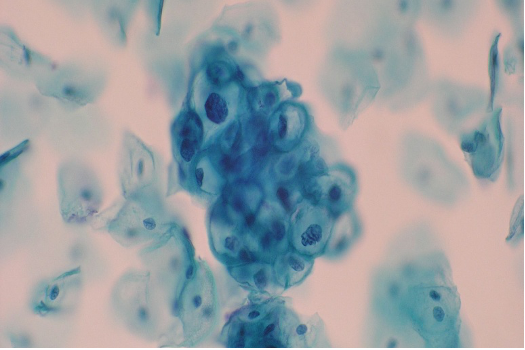

Figs 1 and 2 from a mass in the right hypochondriac region.

Make your diagnosis.

Fig 1 : Giemsa x 100

Fig 2 : Giemsa x 400

Highly suggestive of papillary adeno-carcinoma Endometrium - Shows adequate cellularity with papillae of carcinoma cells showing hyperchromatic and pleomorphic nuclei, highly suggestive of papillary adenocarcinoma of the endometrium.